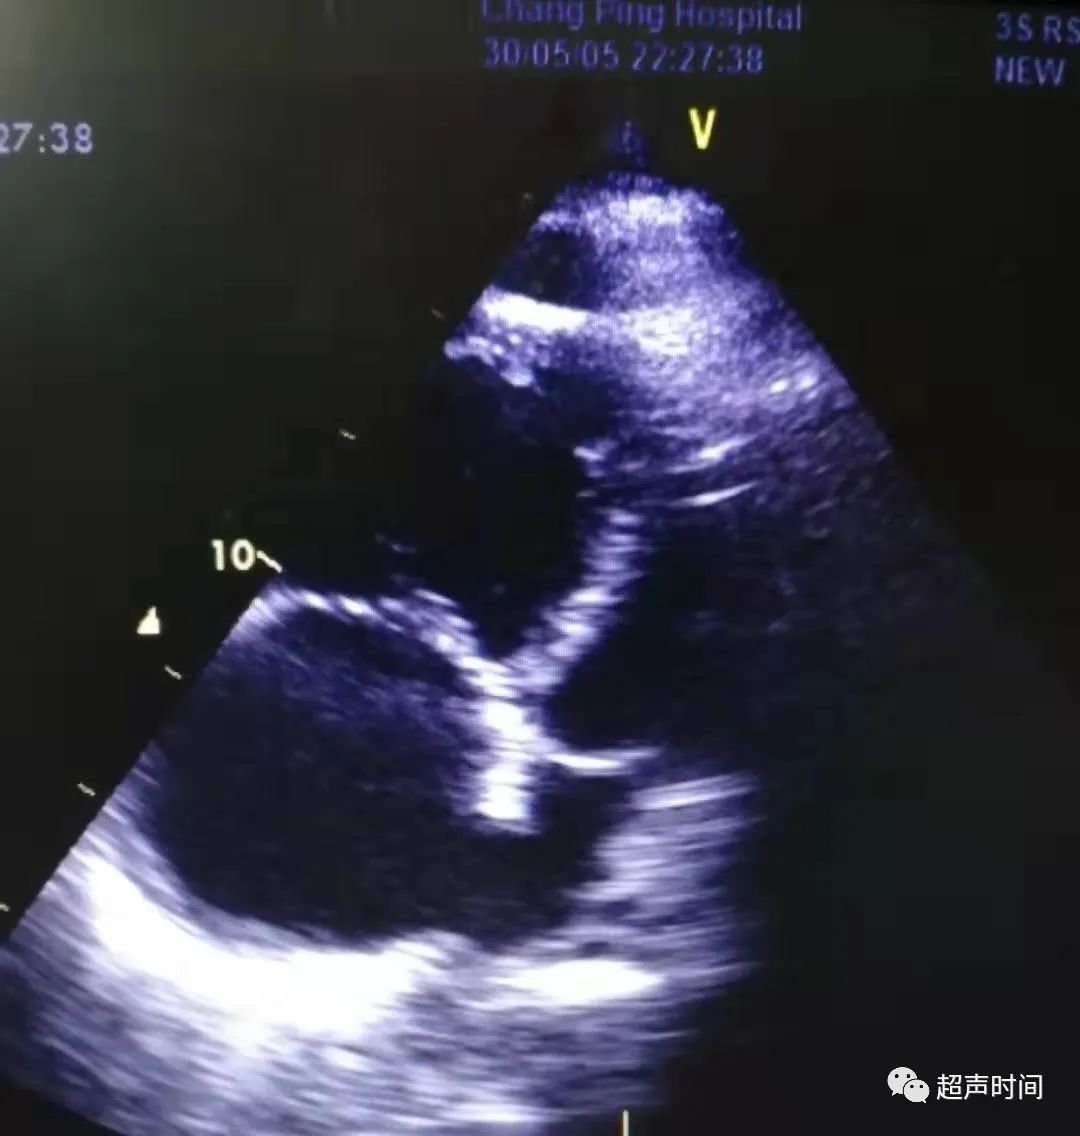

急诊床旁心脏超声所见如下:

图 5~图 7 四腔心切面显示右心明显增大,心尖区少量心包积液,三尖瓣大量反流,估测肺动脉收缩压 127 mmHg

此时,根据超声所见并结合临床,考虑可能存在肺栓塞。于是再回去仔细检查大动脉短轴切面,果不其然: